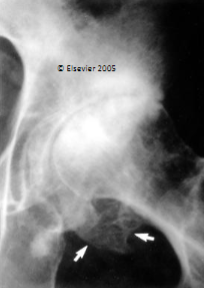

Ankylosing Spondylitis

Ankylosis or “bamboo spine”